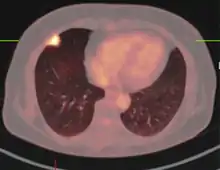

PET scan

If there is an intermediate risk of malignancy, further imaging with positron emission tomography (PET scan) is appropriate (if available). It can be done simultaneously as a CT scan in the form of PET-CT. Around 95% of patients with a malignant nodule will have an abnormal PET scan, while around 78% of patients with a benign nodule will look normal on PET (this is the test sensitivity and specificity).[15] Thus, an abnormal PET scan will reliably pick up cancer, but several other types of nodules (inflammatory or infectious, for example) will also show up on a PET scan. If the nodule has a diameter of less than one centimeter, PET scans are often avoided because of an increased risk of falsely normal results.[15][16][17] Cancerous lesions usually have a high metabolism on PET, as demonstrated by their high uptake of FDG (a radioactive sugar).

PET-CT of a tuberculoma.